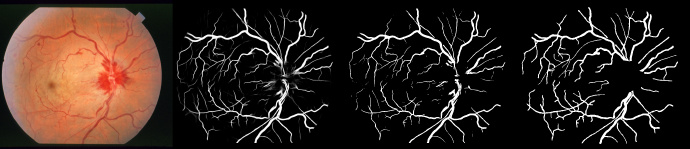

The original image, predicted probability image, predicted binary image and groundtruth

STARE: